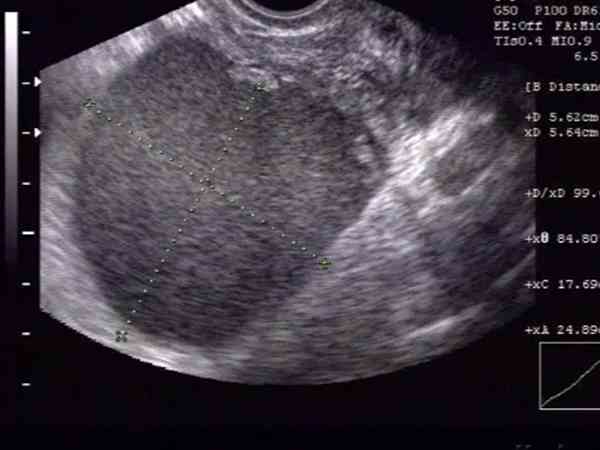

左侧巧克力囊肿是直接做试管还是进行宫腔镜手术需要综合患者的具体情况来,北医三院专家认为,通常情况下,对于囊肿体积小、病情轻的患者,建议是保守治疗,通过药物辅助缓解病情,直接进行试管周期,这样更安全更有保障,对于囊肿体积大于125px的患者,建议是先进行腹腔镜手术。为了方便更多人理解关于巧克力囊肿做试管还是宫腔镜的相关问题,特引用北医三院王洁净医生医患答疑实例:左侧巧克力囊肿近一年半,大小6cm左右...